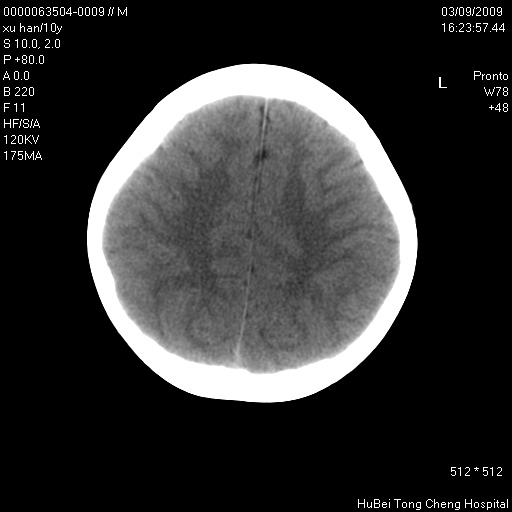

以下是引用道哥在2009-3-9 18:40:00的发言:[br]未见明显异常,必要时mr(dwi)成像。

以下是引用余辉在2009-3-10 11:01:00的发言:[br]考虑双侧海马急性缺氧性损伤